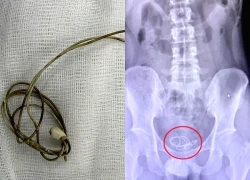

Gắp dây sạc trong bàng quang nam sinh 16 tuổi